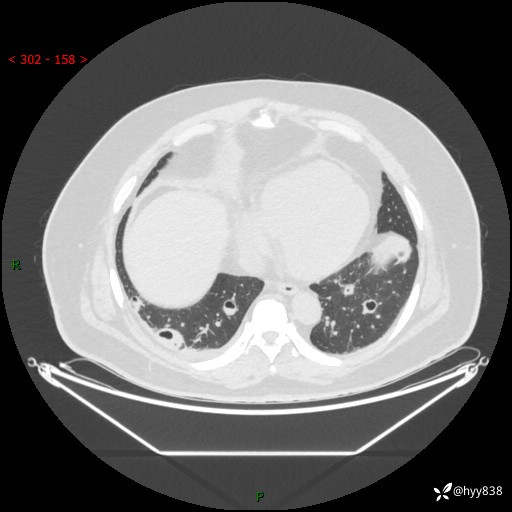

性别:男

年龄:48岁

简要病史:发热来诊(门诊病人)

胸部CT平扫